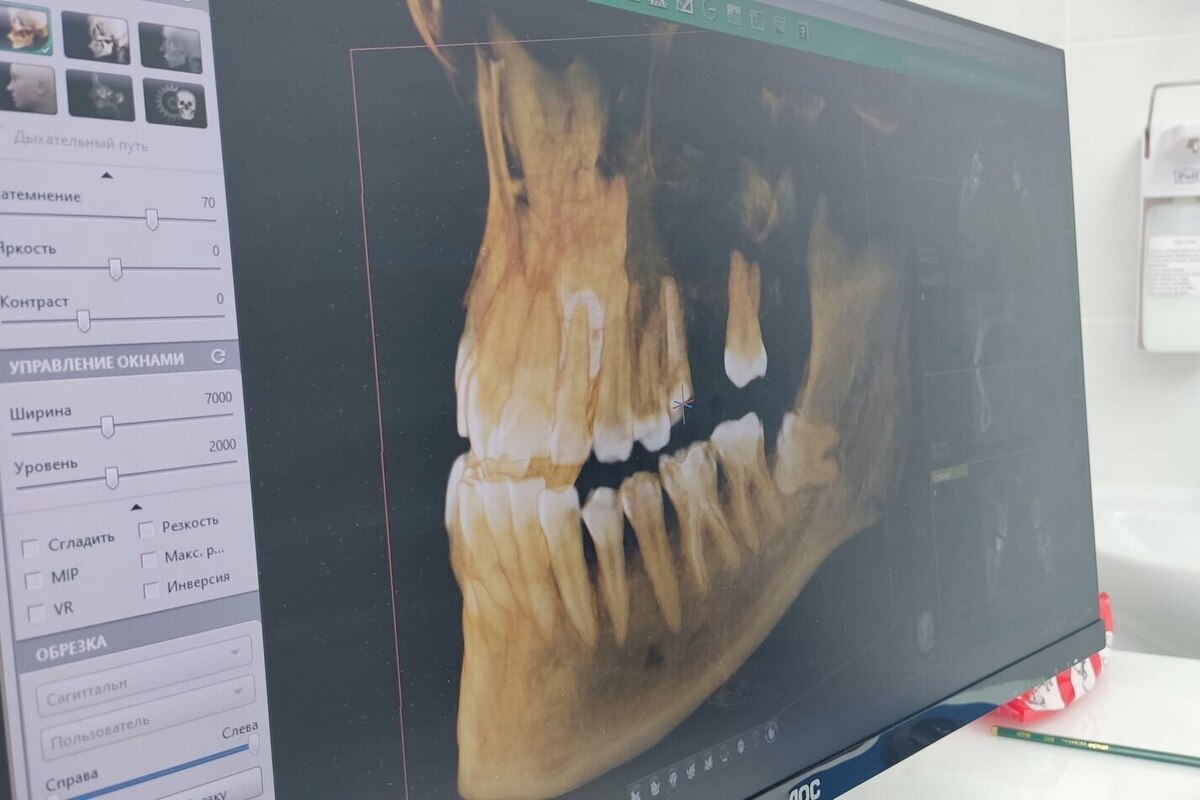

Состояние вашей улыбки тесно связано не только с зубами, но и с осанкой, положением челюсти и здоровьем позвоночника. Об этом рассказали специалисты Киришской стоматологической поликлиники.

Специалисты подчеркивают, что голова – это единая система: если есть проблемы, то это влияет и на челюстной сустав, а также шею и спину. В таких случаях на помощь приходит остеопат, который может значительно улучшить результаты стоматологического лечения:

Если вы слышите щелчки в челюсти, чувствуете боль или вам трудно широко открыть рот, врач может найти первопричину, которая часто кроется в плохой осанке или напряжении других частей тела.

Такое лечение полезно для людей с брекетами, тех, кто готовится к протезированию или имплантации, страдает от скрежета зубами, а также при необъяснимых головных болях или щелчках в челюсти.